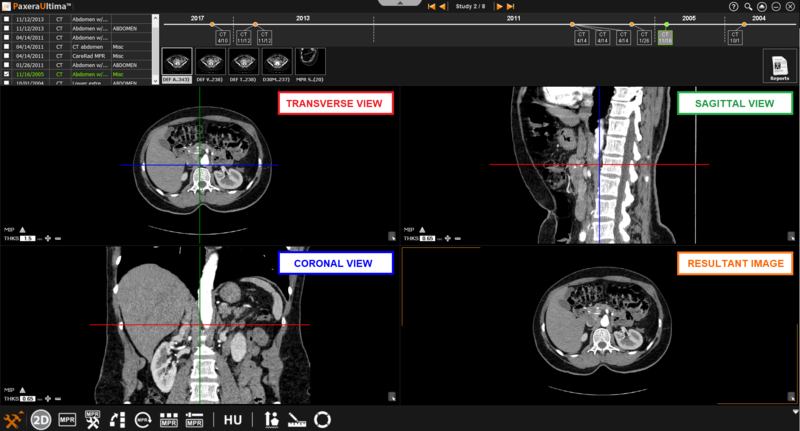

9.4.2. Normal Mode

The normal MPR mode provides three views of the images as shown below: